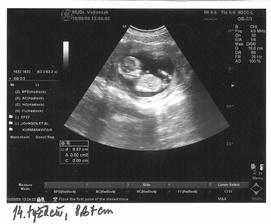

My a náš prvý očakávaný anjelik

Po roku dlhého skúšania sa nám konečne podarilo...Sme s manželom veľmi šťastní a nevieme sa našeho prvo-rodeného bábatka dočkať.